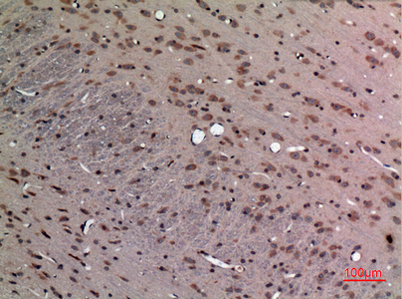

Product name: FGF-12 rabbit pAb

Dilutions: Western Blot: 1/500 - 1/2000. IHC-p: 1:100-300 ELISA: 1/20000. Not yet tested in other applications.

Immunogen: The antiserum was produced against synthesized peptide derived from the Internal region of human FGF12. AA range:31-80

Cellular localization: Nucleus .